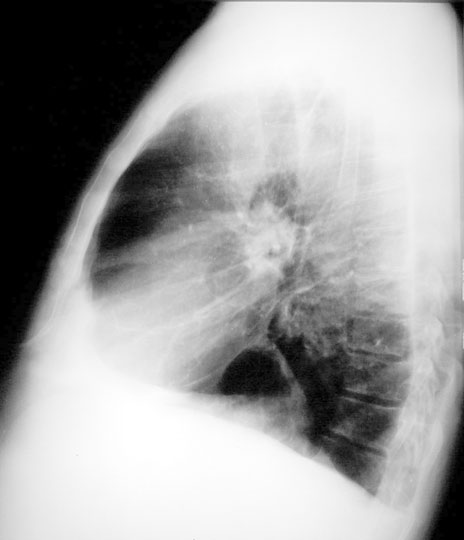

Case 3 Labeled Image What is the differential for thick walled cavity?

Labeled Image What is the differential for thick walled cavity?